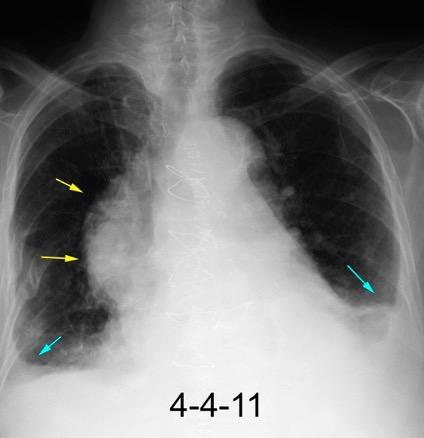

30 años

Borramiento de la banda PARA-aórtica por AdenoCa. de LII, no visible en 2005

Colapso de LII. TC: secreciones bronquiales.

Endoscopia tapón mucopurulento extraído

Borramiento parcial por Ca. epidermoide.